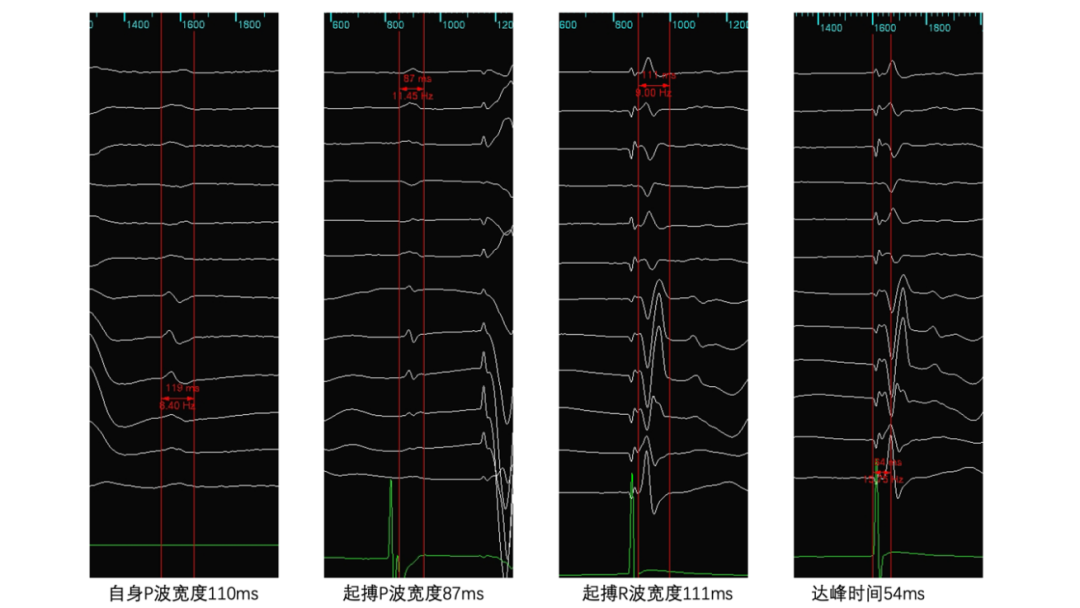

该手术以巴赫曼束区域起搏(Bachmann束起搏)联合左束支区域起搏为核心技术,通过精准定位,实现了从心房到心室的双传导束全生理性起搏。余华介绍,相较于传统的双腔起搏方式(电极多放置于右心耳、右心室间隔部)、单纯的巴赫曼束区域起搏以及单纯左束支区域起搏,全生理性起搏力求将心房、心室电极都植入到人体自身的传导束系统上,能最大程度地模拟心脏自然传导激动顺序。虽然该手术操作难度较高,过程要求更加精准细致,但该技术不仅能显著优化患者心脏泵血效率、改善心功能、降低新发房颤的风险,还能有效避免传统起搏方式带来的心脏电极穿孔等风险,为患者带来更优的远期预后。